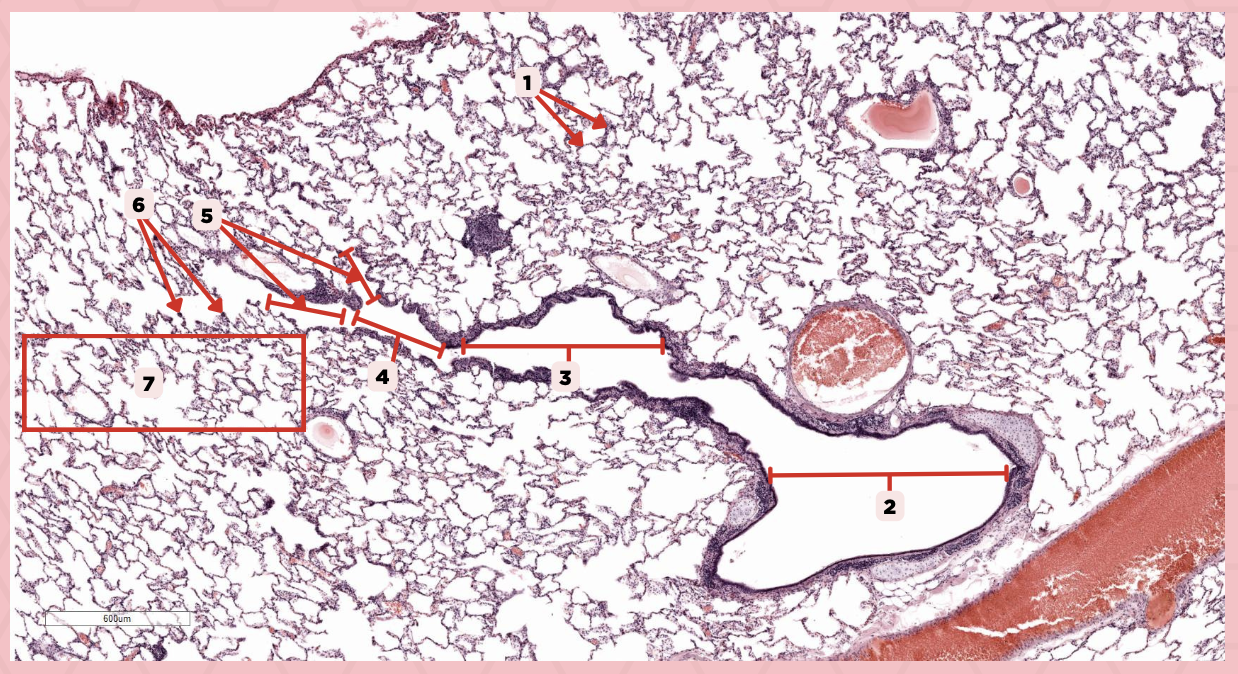

Interalveolar septa

Identify the structure labeled as 1.

Intrapulmonary bronchi

Identify the structure labeled as 2.

Bronchiole

Identify the structure labeled as 3.

Terminal bronchiole

Identify the structure labeled as 4.

Respiratory bronchiole

Identify the structure labeled as 5.

Alveolar ducts

Identify the structure labeled as 6.

Alveolar sacs

Identify the structure labeled as 7.

Bigger and smaller intrapulmonary bronchi

What are the two types of intrapulmonary bronchi?

Pseudostratified epithelium (bigger bronchioles), Simple columnar or cuboidal (smaller)

What are the types of epithelium in No. 3?

Deoxygenated blood

What type of blood does vessel No. 1 carry?

Connective tissue septae

Where would No. 2 be located?

Pulmonary artery

Identify the structure labeled as 1.

Tributary of pulmonary vein

Identify the structure labeled as 2.

Oxygenated blood

What type of blood does this vessel supply?